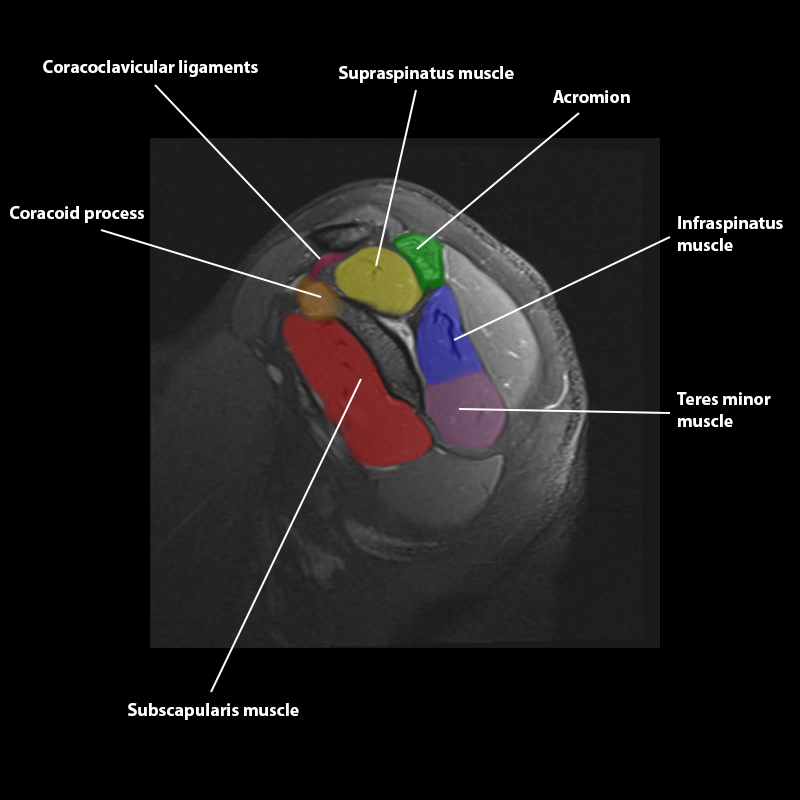

Shoulder MRI Anatomy